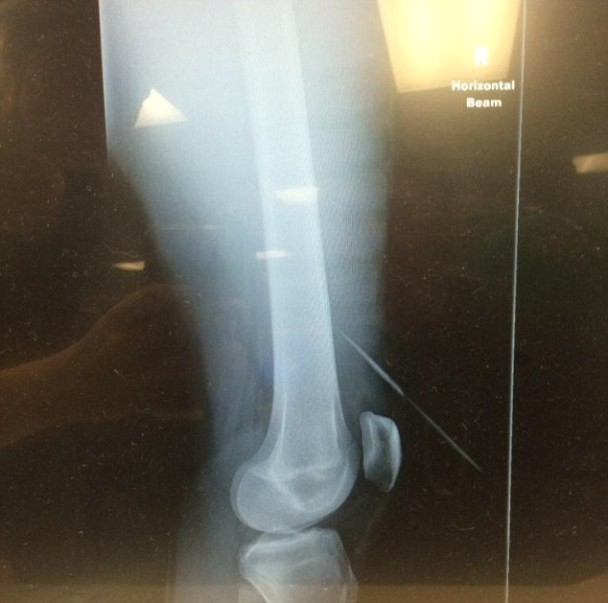

尖刺刺中贾米森的右腿

从X光片可见,尖刺仅仅避过贾米森的骨头位置。

岂料贾米森送院后仍要继续等,皆因医院大停电,最终要他等足24小时才进行2小时手术将尖刺拔出。从X光片可见,尖刺与贾米森的右膝仅差7厘米,避过骨头位置。贾米森料于周一出院。